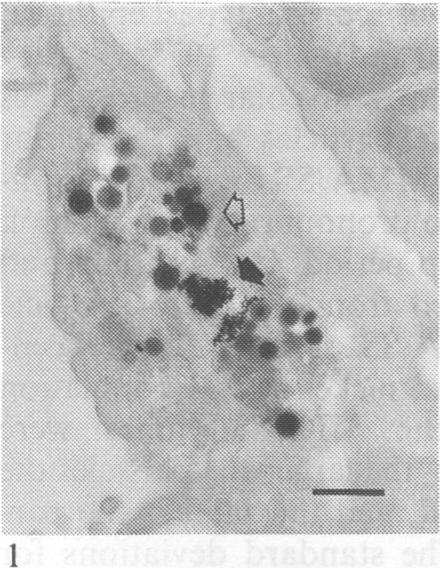

The dissolution of stainless steel welding fumes produced by manual metal arc (MMA) and metal inert gas (MIG) techniques was studied by transmission electron microscopy and quantitative x ray microanalysis in the lungs of rats after inhalation exposure. Rats exposed to stainless steel fumes generated by MMA were found to have two particle populations of different behaviour in their lung tissue. The particles of the principal population (size 100-250 nm) dissolved in both alveolar macrophages and type 1 epithelial cells in about two months. Fast and slowly dissolving components of chromium, manganese, and iron were detected within these particles; they obviously represent different chemical compounds. The particles of the minor population (size 5-100 nm) showed no signs of dissolution during three months follow up. Rats exposed to stainless steel fumes generated by MIG had only one particle population in their lung tissue; they were similar to those of the minor population in the MMA/SS fumes and no solubility could be detected within three months.

通过透射电子显微镜和定量X射线微分析,研究了手工金属电弧焊(MMA)和金属惰性气体保护焊(MIG)技术产生的不锈钢焊接烟尘在大鼠吸入暴露后肺组织中的溶解情况。发现暴露于MMA产生的不锈钢烟尘的大鼠肺组织中有两种行为不同的颗粒群体。主要群体的颗粒(尺寸为100 - 250纳米)在大约两个月内溶解于肺泡巨噬细胞和I型上皮细胞中。在这些颗粒中检测到铬、锰和铁的快速和缓慢溶解成分;它们显然代表不同的化合物。次要群体的颗粒(尺寸为5 - 100纳米)在三个月的随访期间没有溶解迹象。暴露于MIG产生的不锈钢烟尘的大鼠肺组织中只有一种颗粒群体;它们与MMA/SS烟尘中次要群体的颗粒相似,在三个月内未检测到溶解性。